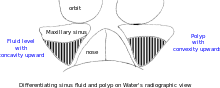

| Maxillary sinusitis | ![]() Differentiating pathology in maxillary sinus

| Polyp |